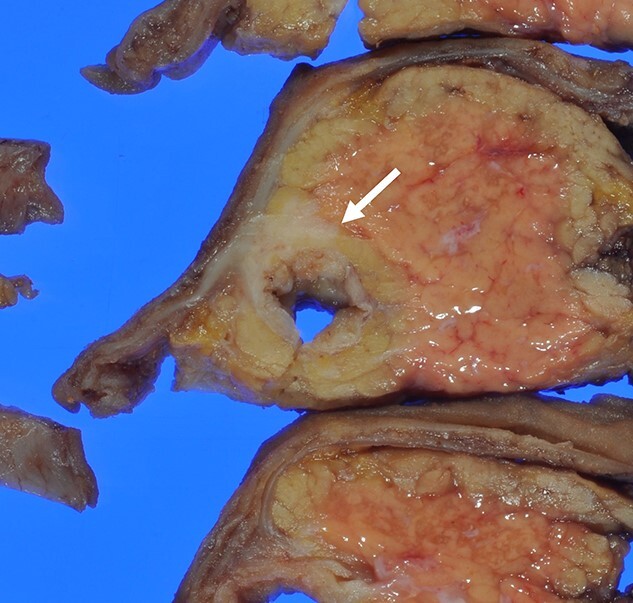

Macroscopically, there was a gray invasive nodular tumor measuring 19 × 18 × 15 mm at the distal CBD (Fig. 4). Histopathological examination showed that the tumor comprised two components; well-differentiated adenocarcinoma of the CBD mucosa (20%) and proliferation of small atypical cells forming follicular nests with invasion around the CBD wall (80%) (Fig. 5a and b). The invasion extended to the pancreas and duodenal muscular layer. Immunohistochemical examination revealed that the solid proliferative lesions of small atypical cells were positive for chromogranin A and synaptophysin (Fig. 6a–c). The Ki-67 index was ~80% (Fig. 6d). No lymph node metastasis was detected. The patient was finally diagnosed with small-cell NEC (pT2N0M0, pStage I B) of the EHBD. R0 resection was achieved pathologically and there was no recurrence for 4 months after surgery.